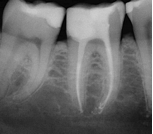

Surgical Exposure of ECIR with External Cervical Root Repair, Conventional RCT with Prefab Post

MB Root Amputation